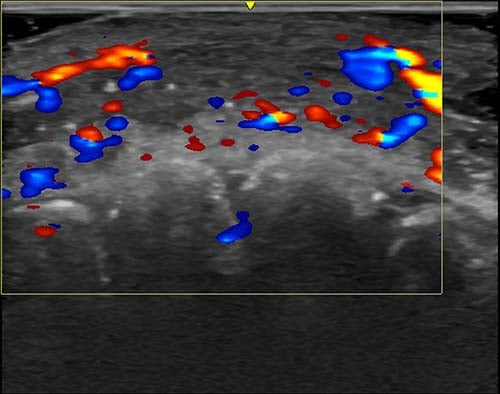

Clinics are now being advised to carry out ultrasounds before injecting dermal fillers to see where the vessels are located.

In just under half of cases, ultrasound scans showed absent flow to blood vessels that connect superficial to deep arteries in the face. In over a third of cases, flow was absent in major blood vessels.

To treat filler-related complications, an enzyme called hyaluronidase is injected to break down the hyaluronic acid filler material. Ultrasound also helps guide clinicians to the area that needs treating.

âIf injectors are not guided by ultrasound, they treat based on where the clinical findings are and inject blindly,â Dr Sigrist added.

âBut if we can see the ultrasound finding, we can target the exact place where the occlusion occurs. Rather than flooding the area with hyaluronidase, we can do guided injections that use less hyaluronidase and provide better treatment results.â

Ultrasound is also a useful tool for guiding the filler injections themselves and can help with precision, so that less is needed and complications are less likely from the start, she explained.